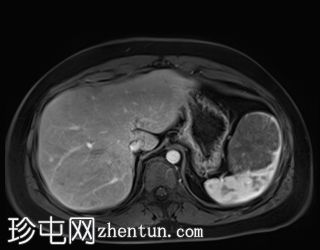

轴位

T2加权像

T1低信号,T2低信号为主的脾脏肿块,内部可见T2高信号分隔,呈进行性强化。肿块中央可见星状瘢痕。

脾脏硬化性血管瘤样结节性转化(SANT),9.8 cm肿块

顾名思义,脾脏硬化性血管瘤样结节性转化(SANT)是一种纤维性血管病变。本病例展示了SANT的一些典型影像学特征,包括边界清晰的病灶,中央可见瘢痕,以及呈放射状进行性强化。这些特征使得术前MRI诊断较为明确。尽管SANT是一种良性病变,但大多数患者仍需行脾切除术以明确病理诊断。